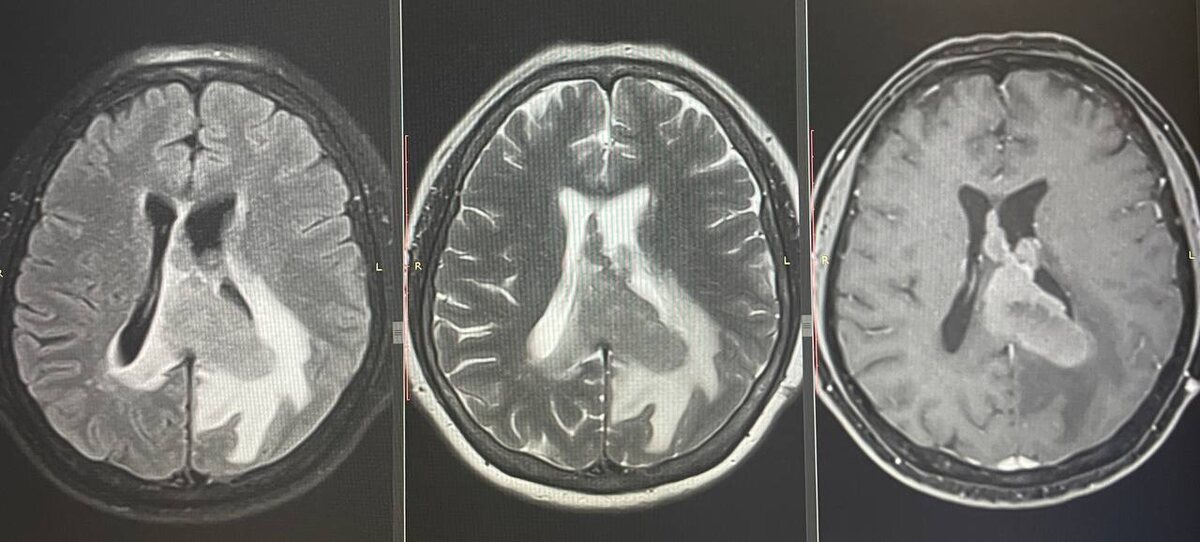

Публикую дополнение к выше описанному случаю. МРТ ГМ того же пациента. Исследование обладает большей информативностью: последовательности FLAIR, T2 и T1 с контрастным усилением дают более наглядную визуализацию лимфомы.